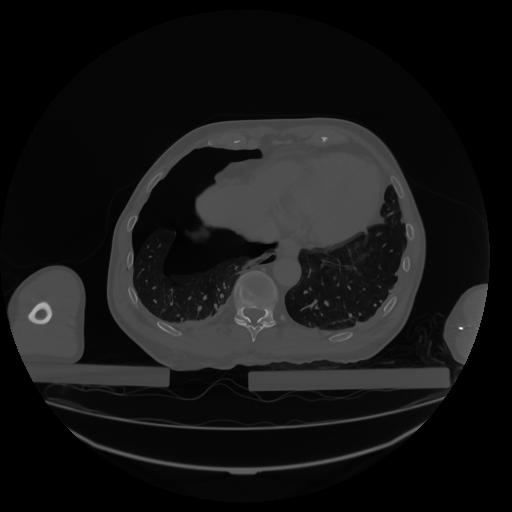

34 CUERPO,CE,Vol,1.0,CUERPO,,